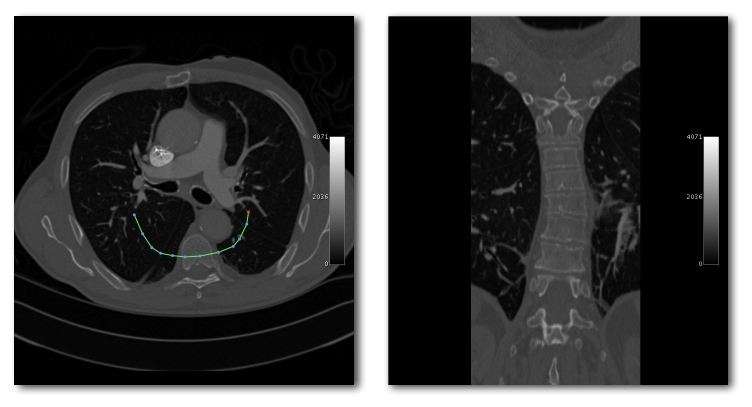

- Curved Reconstruction

- Curved MPRs can be used for the reconstruction of more complex perspectives, as illustrated in the next figure:

- Here a curve (highlighted in green) can been positioned in the axial images (left panel) to define a curved surface which extends through the voxel data in the z-direction, and voxels from this data can be reconstructed into a two-dimensional image (right panel). Note that more complex curves than the one illustrated can be generated so that, for instance, the three-dimensional course of a major blood vessel can be isolated, or CT head scans can be planarized for orthodontic applications.